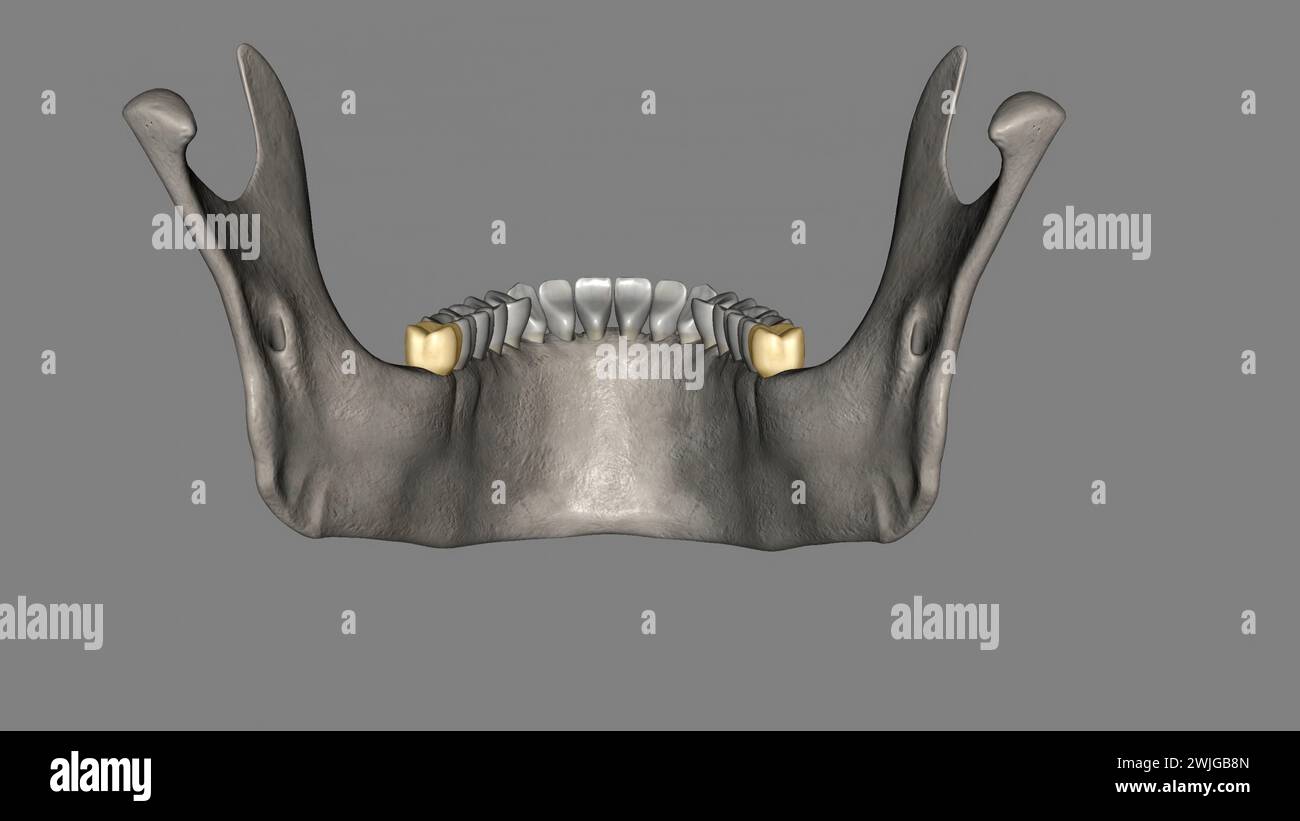

The mandibular third molar is also referred as the wisdom tooth 3d What Are Wisdom Teeth Third Molar When do wisdom teeth come in? Molars are designed to sustain great amounts of force. Often the last set of teeth to emerge in the mouth,. wisdom teeth are the third and final set of molars that most people get in their late teens or early twenties. wisdom teeth, the third molars at the back of the mouth,. What Are Wisdom Teeth Third Molar.